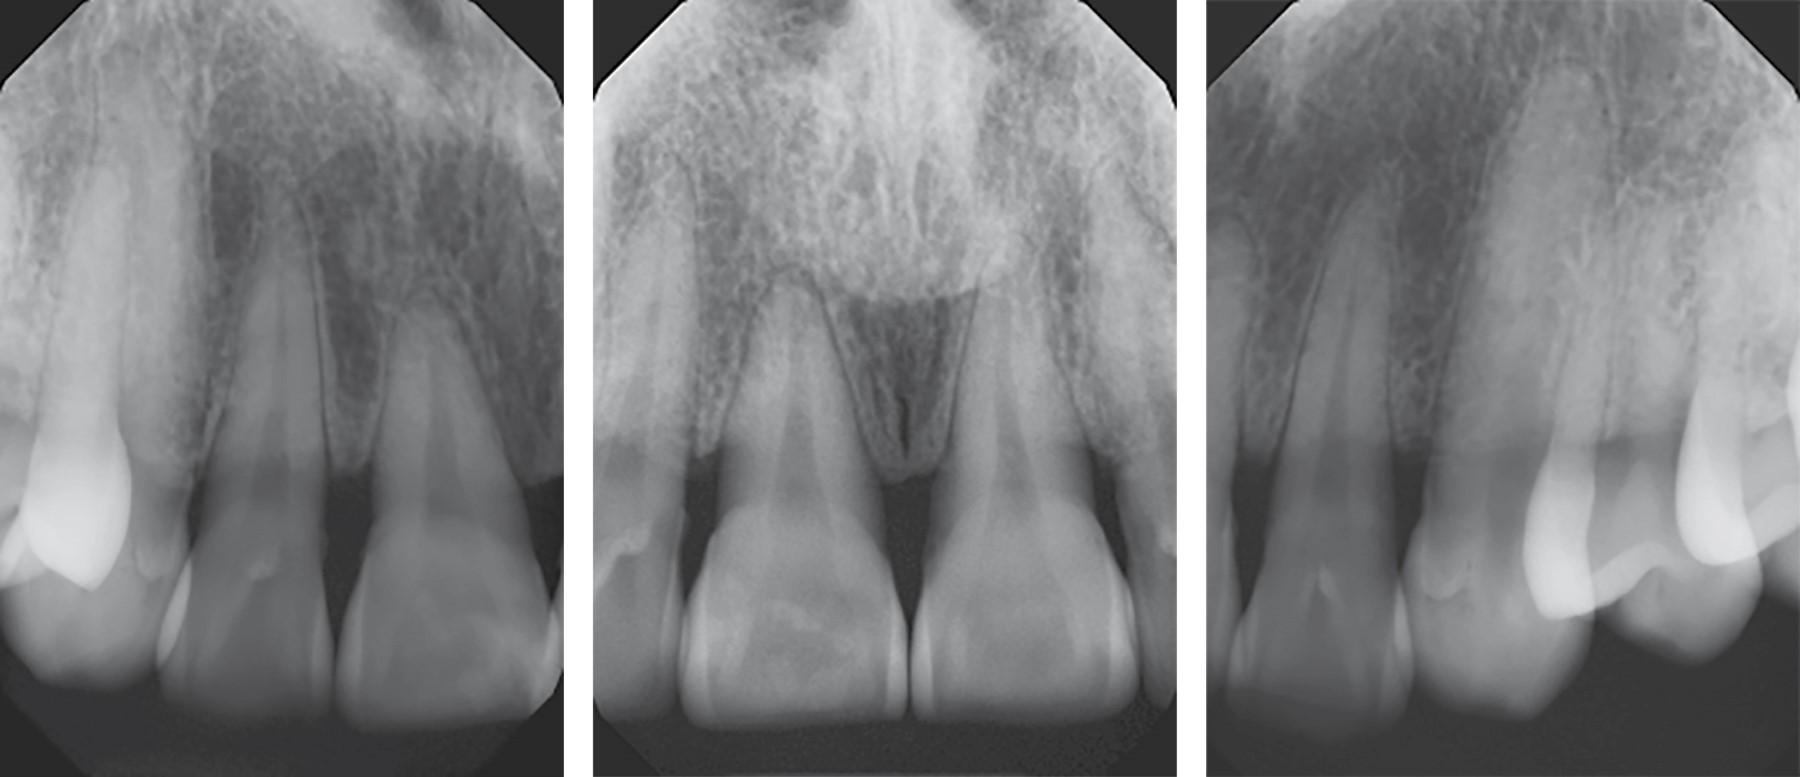

En la radiografía periapical intraoral se observa pérdida ósea de alrededor del 30% en relación a los órganos dentarios 11, 12, 21 y 22. No se observan radiopacidades dentro de la tumoración de partes blandas (Figura 2).

Figura 2